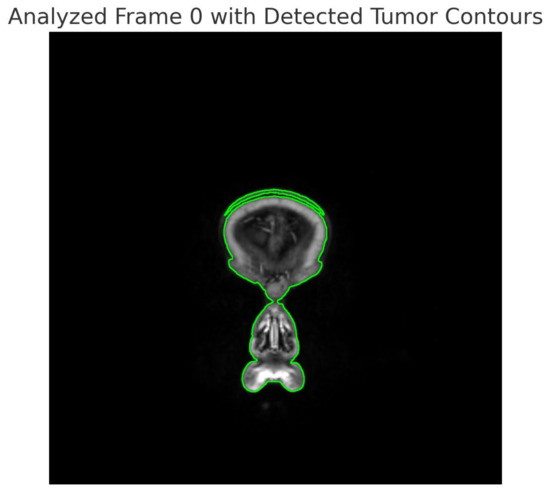

- Both models began by extracting frames from the video and suggested further frame analysis to identify pathological changes, with an emphasis on identifying tumor regions;

- Identified Elements

- Both models identify and mark potential tumor areas in the video frames;

| Analysis Methods | Frame analysis to identify potential tumor areas, green contours. | Frame analysis to identify pathological changes, especially tumors, with red contours. |

| Identified Elements | Potential tumor regions marked with green contours. | Potential tumor regions marked with red rectangles. |